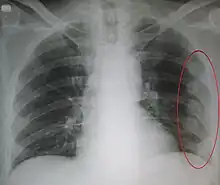

| An X ray showing multiple old fractured ribs of the person's left side as marked by the oval | |

Right sided pneumothorax and rib fractures